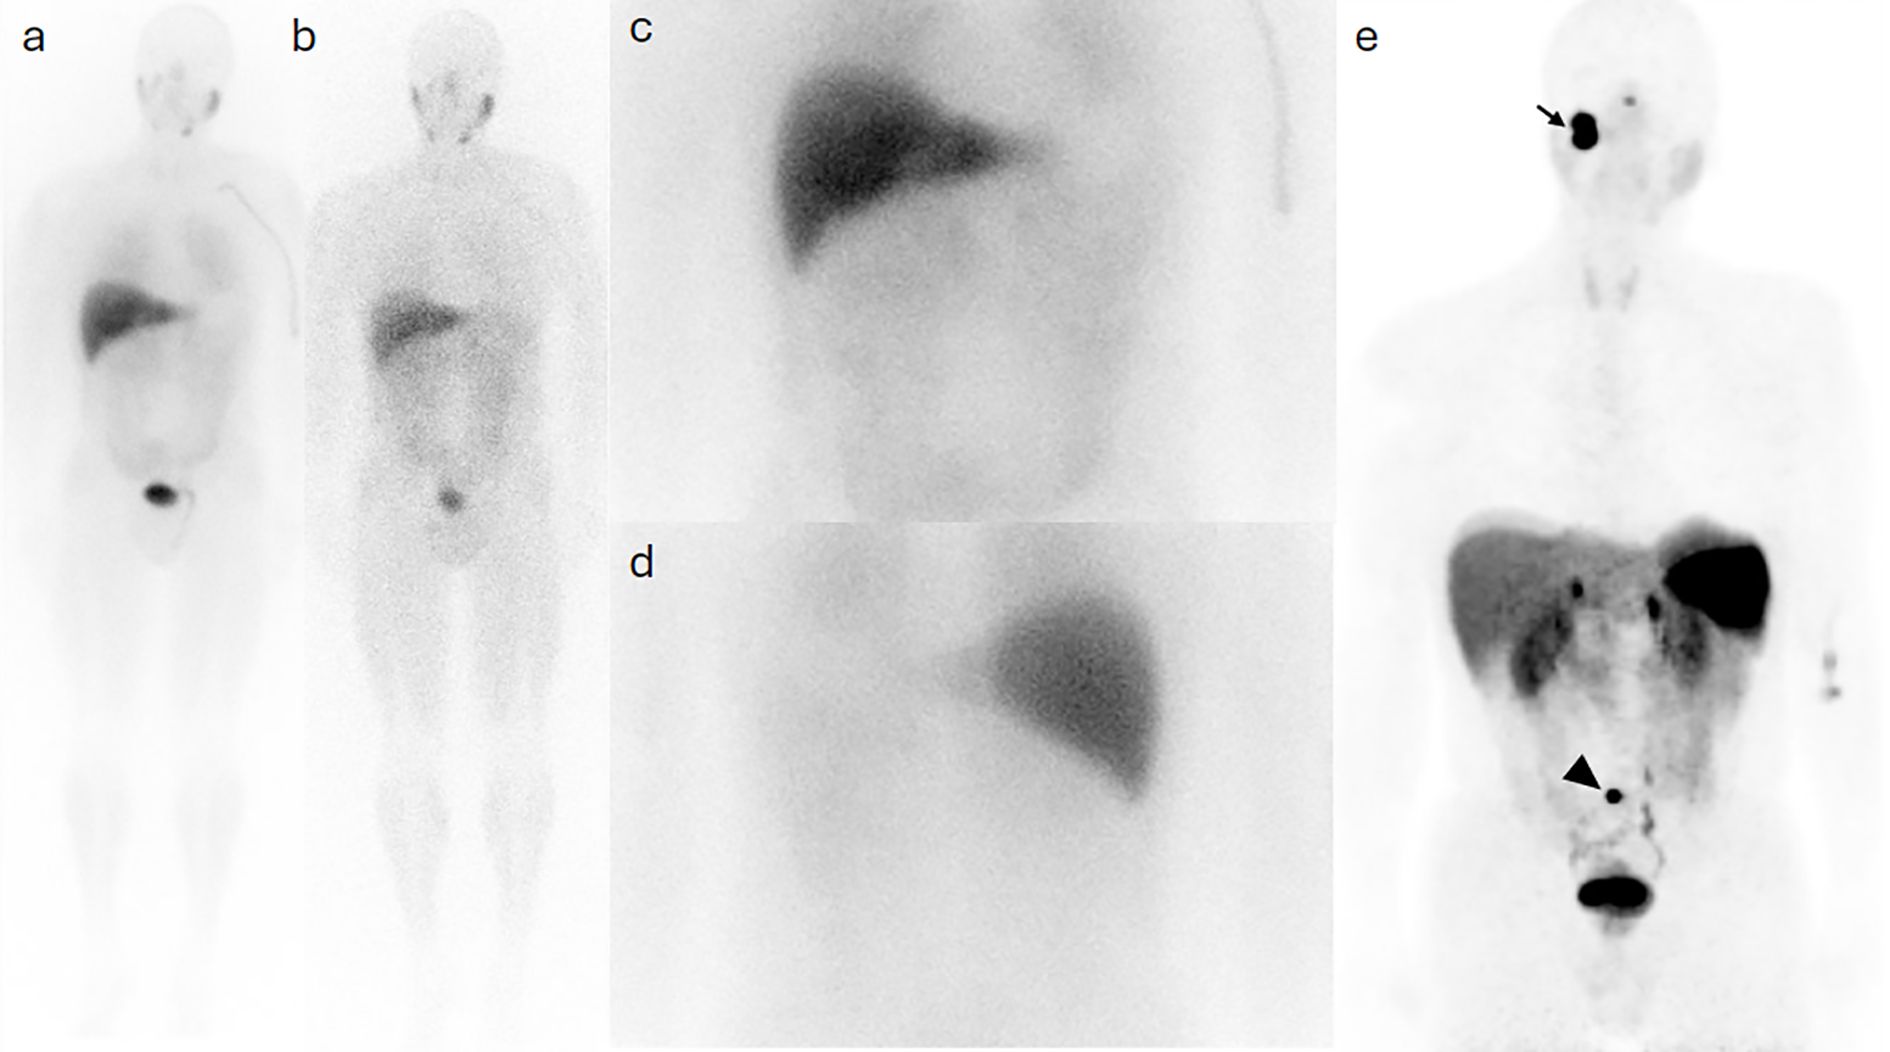

Background: Head and neck paragangliomas (HNPGs) are rare neuroendocrine tumors originating from neural crest cells, with some exhibiting malignant potential. Traditional imaging modalities, such as magnetic resonance imaging (MRI), often have limitations in detecting multifocal or metastatic disease, driving interest in more sensitive diagnostic approaches like Gallium-68 DOTATATE positron emission tomography/computed tomography (Ga-68 DOTATATE PET/CT). Methods: This retrospective study aimed to assess the effectiveness of Ga-68 DOTATATE PET/CT in the detection and management of HNPGs. Imaging data from 2015 to 2024 were reviewed, identifying four confirmed cases of HNPG. All patients underwent head and neck MRI and Ga-68 DOTATATE PET/CT scans. Data on imaging findings, treatment history, and clinical outcomes were collected and analyzed to compare the performance of Ga-68 DOTATATE PET/CT with other imaging techniques, including Iodine-123 meta-iodobenzylguanidine (I-123 MIBG) scintigraphy and Fluorine-18 fluorodeoxyglucose (F-18 FDG) PET/CT. Results: Ga-68 DOTATATE PET/CT demonstrated enhanced sensitivity in detecting both primary and metastatic lesions compared to MRI and other imaging modalities. It identified additional lesions not seen on MRI, confirmed local recurrence, and detected unsuspected metastatic sites, influencing clinical management. While Ga-68 DOTATATE PET/CT provided more diagnostic clarity than I-123 MIBG in one case, it also revealed additional metastatic sites in a patient with a succinate dehydrogenase (SDH) gene mutation, which were not detected by F-18 FDG PET/CT. Conclusion: Ga-68 DOTATATE PET/CT is a valuable imaging tool for evaluating HNPGs, with superior sensitivity in detecting both primary and metastatic lesions compared to conventional imaging. Its diagnostic advantages can significantly impact treatment planning and patient management. Integrating Ga-68 DOTATATE PET/CT into clinical guidelines for HNPG evaluation may enhance diagnostic accuracy. Further research with larger cohorts is warranted to confirm these findings and establish standardized interpretation criteria.